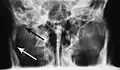

Computed tomography

Computed tomography is the most sensitive and specific of the imaging techniques. The facial bones can be visualized as slices through the skeletal in either the axial, coronal or sagittal planes. Images can be reconstructed into a 3-dimensional view, to give a better sense of the displacement of various fragments. 3D reconstruction, however, can mask smaller fractures owing to volume averaging, scatter artifact and surrounding structures simply blocking the view of underlying areas.

Research has shown that panoramic radiography is similar to computed tomography in its diagnostic accuracy for mandible fractures and both are more accurate than plain film radiograph.[12] The indications to use CT for mandible fracture vary by region, but it does not seem to add to diagnosis or treatment planning except for comminuted or avulsive type fractures,[13] although, there is better clinician agreement on the location and absence of fractures with CT compared to panoramic radiography.[14]

3D CT reconstruction of mandible fracture, white arrow marks fracture, red arrow marks moderate displacement and open bite